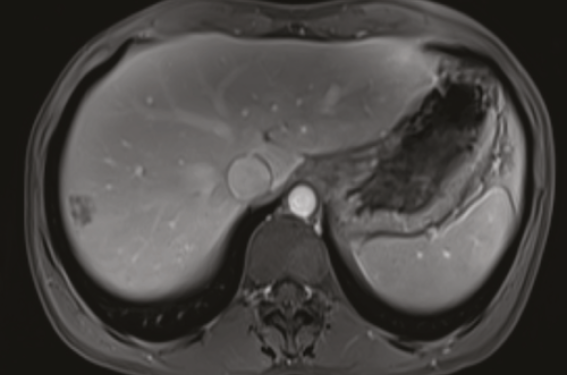

Une nouvelle étude clinique a été mis en place grâce aux efforts des CHU de Nîmes et de Montpellier : MARGIN pour le traitement des Métastases hépatiques par Ablation percutanée dans le cancer coloRectal avec Guidage par Imagerie par aNgio-CT.

Cette étude va évaluer l’efficacité de deux techniques de guidage (scanner injecté standard vs porto-scanner avec angio-CT) pour le traitement par thermoablation des métastases hépatiques de cancer colorectal (CCR). Il s’agit d’une étude contrôlée randomisée en simple aveugle. Après la survenue d’un...